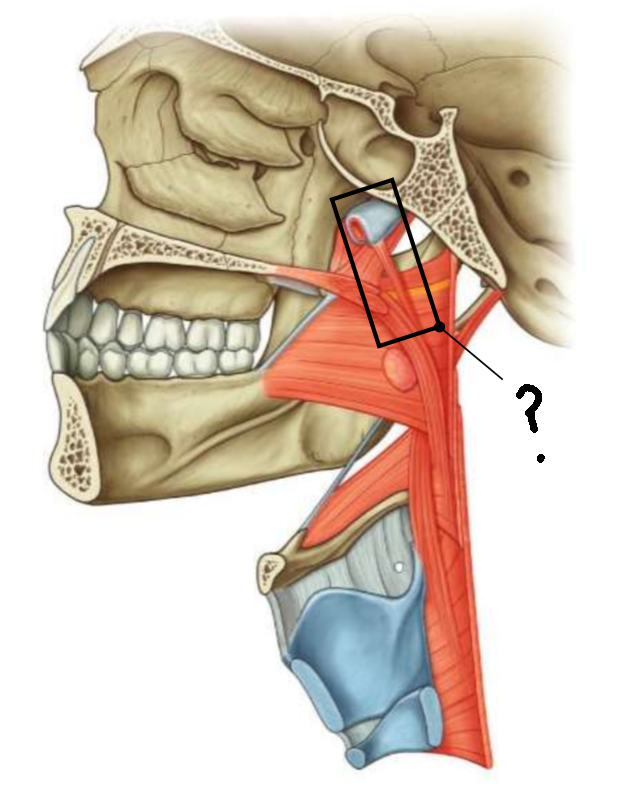

What muscle is this?

inferior constrictor

Which part of the muscle is 1?

thyropharyngeus

Which part of the muscle is 2?

cricopharyngeus

What are the attachments of this muscle?

oblique line of thyroid cartilage, cricothyroid tendon, cricoid cartilage → pharyngeal raphe

What is in the rectangle?

pharyngeal raphe

What is in the circle?

killians dehiscence

What is in the rectangle?

pterygomandibular raphe